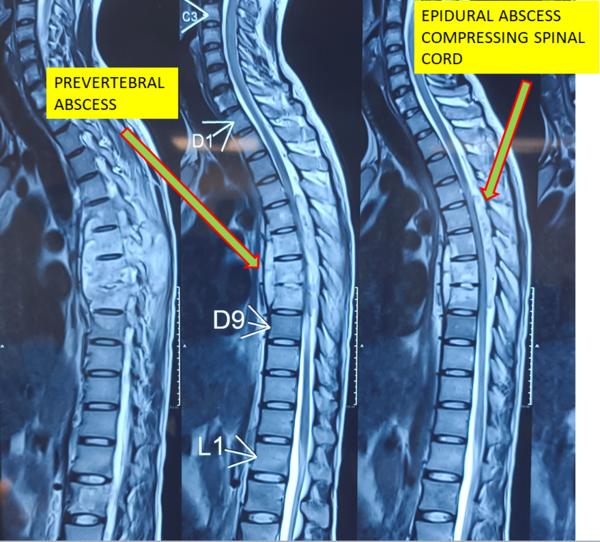

Best Spine Surgeon in Pune Best Spine Specialist in Pune Dr. Nitish Agarwal

View Details